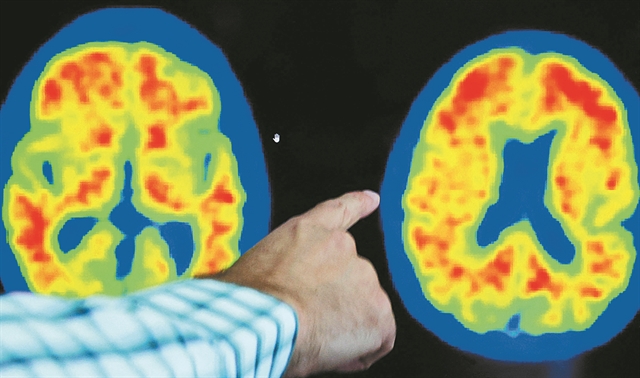

Και τα δύο φάρμακα δρουν μειώνοντας τη συσσώρευση κολλώδους αμυλοειδούς πλάκας στον εγκέφαλο, γνωστής ως β-αμυλοειδές, η οποία βρίσκεται στο επίκεντρο μιας οξείας επιστημονικής συζήτησης σχετικά με το τι προκαλεί τη νόσο Αλτσχάιμερ. Σχεδόν δύο δωδεκάδες κλινικές δοκιμές φαρμάκων που προσπαθούν να θεραπεύσουν τη νόσο Αλτσχάιμερ μειώνοντας αυτές τις πλάκες έχουν αποτύχει από το 2003, προκαλώντας σκεπτικισμό σε ορισμένους ειδικούς ότι η αφαίρεση του αμυλοειδούς μπορεί να επιβραδύνει την εξέλιξη της νόσου.

Η αμφιλεγόμενη έγκριση από τον FDA ενός άλλου φαρμάκου που μειώνει το αμυλοειδές και ονομάζεται αδουκανουμάμπη το 2021, παρά τα αντικρουόμενα στοιχεία ότι επιβραδύνει τον ρυθμό της γνωστικής έκπτωσης, φούντωσε περαιτέρω τη συζήτηση. Εκπρόσωπος της εταιρείας Lilly δήλωσε στους «Financial Times» ότι τα αποτελέσματα των δοκιμών της δονανεμάμπης και της λεκανεμάμπης μαζί αποδεικνύουν την «υπόθεση του αμυλοειδούς», τη θεωρία που υποστηρίζει ότι οι κολλώδεις πλάκες αμυλοειδούς είναι η κύρια αιτία της νόσου Αλτσχάιμερ.

Η δονανεμάμπη έδειξε ισχυρή αποτελεσματικότητα στην αφαίρεση των πλακών στη δοκιμή, με λίγο περισσότερους από τους μισούς συμμετέχοντες να μπορούν να ολοκληρώσουν την πορεία της θεραπείας τους εντός ενός έτους, καθώς πέτυχαν τον στόχο για την απομάκρυνση του αμυλοειδούς. Η Ενωση για την Αλτσχάιμερ ανακοίνωσε ότι τα αποτελέσματα της δοκιμής ήταν τα «ισχυρότερα» που έχουν κυκλοφορήσει μέχρι σήμερα για ένα φάρμακο που μειώνει το αμυλοειδές και υποδηλώνουν ένα «σημείο καμπής» για τη θεραπεία της νόσου.